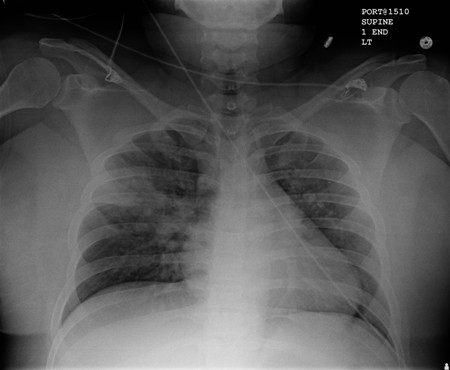

[Figure caption and citation for the preceding image starts]: Radiografia torácica portátil com opacidades bibasilares, com quadro mais desfavorável no lado direito que no esquerdo, em um paciente com pneumonia hospitalarDo acervo pessoal do Dr. F. W. Arnold, Divisão de Doenças Infecciosas do Departamento de Medicina, Escola de Medicina da Universidade de Louisville [Citation ends].